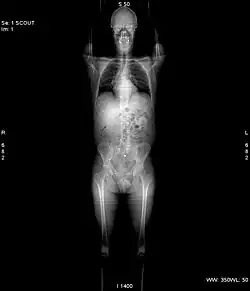

Before the actual scan, a topogram, also known as a scout image or localizer image, is taken which is a low-dose, low-resolution radiographic image. This initial image helps to plan the coverage and orientation of the subsequent CT scan. The topogram provides a preliminary overview of the area to be imaged, allowing technologist to plan the scan.[132] Since, Topograms have a larger field of view than main scan, they can also play a role in revealing significant findings outside the scan field of view.[133]